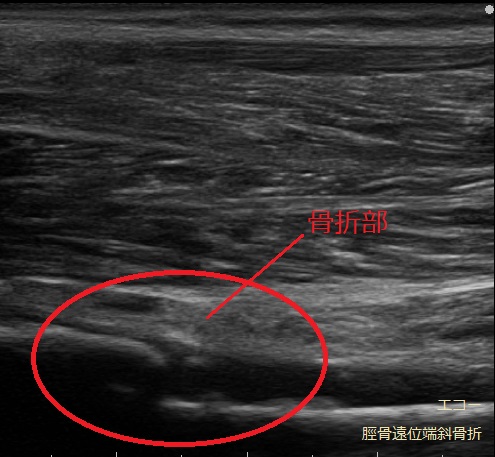

超音波(エコ-)検査は、骨・靭帯・筋肉・腱などの病態を診る検査装置です。

関節や筋肉を実際に動かしつつ観察できるため、状態の変化や回復の様子を把握しながら進めていきます。

レントゲン画像には映りにくい筋肉や腱、靭帯などの状態に加え、骨の様子もあわせて確認できます。